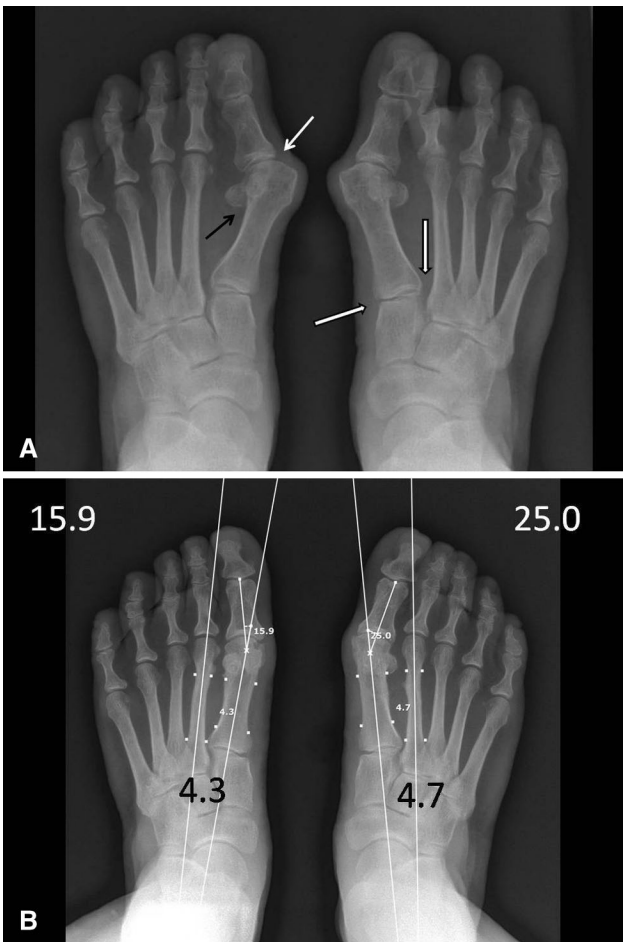

▲图示(A)64 岁女性患者术前站立位 X 线片示:双足重度第一跖骨内翻,跖趾关节(白色实心箭头)与跖楔关节(白边黑色箭头)对位不良,跖籽分离(黑色实心箭头),且右足第二跖趾关节背侧脱位;术前美国足踝外科协会(AOFAS)拇趾评分 55 分。(B)术后 2 年站立位 X 线片示:第一跖骨间间隙缩小,跖趾关节与跖楔关节对位恢复正常,跖籽关系恢复正常,右足第二跖趾关节脱位减轻;左足 AOFAS 拇趾评分 100 分,右足 93 分;双足足趾跖趾关节角分别为 15.9° 和 25.0°,跖骨间角分别为 4.3° 和 4.7°。